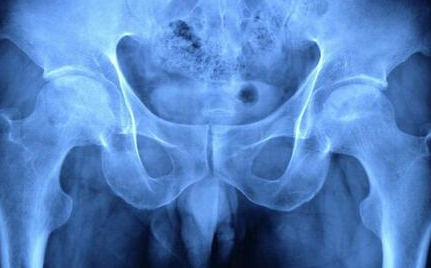

从股骨头坏死早期症状图中可以看出哪些早期股骨头坏

河南股骨头坏死医院介绍股骨头坏死为常见的骨关节病之一。若不及时治疗可能会导致关节的受…[详情]